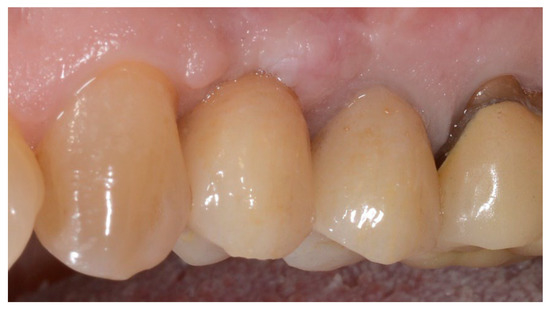

3. Results

3.1. Implant Failure, Complications, and Patients’ Satisfaction